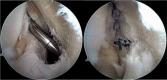

Conclusion: A capsular opening to the semimembranosus-medial head gastrocnemius bursa is a commonly found normal anatomic variant. It is thought that this can lead to the formation of a popliteal cyst in the presence of chronic knee effusions as a result of intra-articular pathology. Management of symptomatic popliteal cysts is conservative. The intra-articular pathology should be first addressed by arthroscopy. If surgical excision later becomes necessary, a limited posteromedial approach is often employed. Other treatments, such as arthroscopic debridement and closure of the valvular mechanism, are not well studied and cannot yet be recommended.